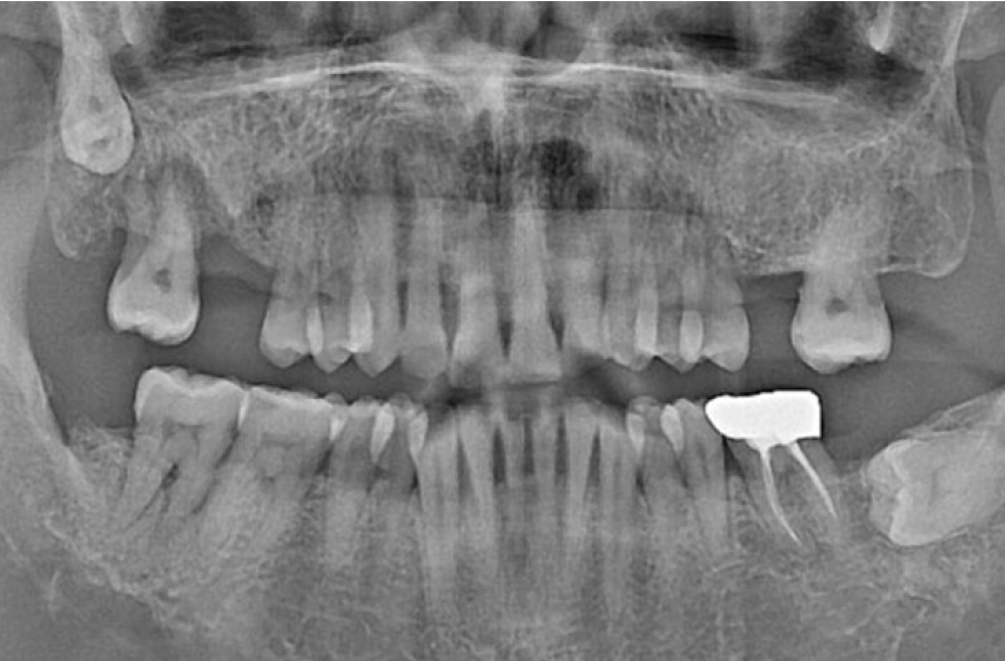

왼쪽 하악 매복 사랑니 발치 Before X-Ray

치료시작일

2020.05.24

AFTER

왼쪽 하악 매복 사랑니 발치 After X-Ray

치료종료일

2020.06.29

왼쪽 하악 매복 사랑니 발치